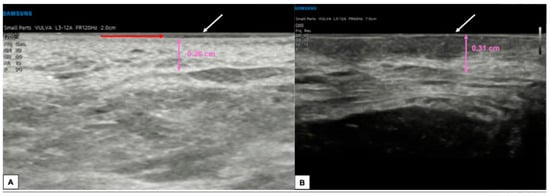

6.1. Epidermis

6.2. Dermis